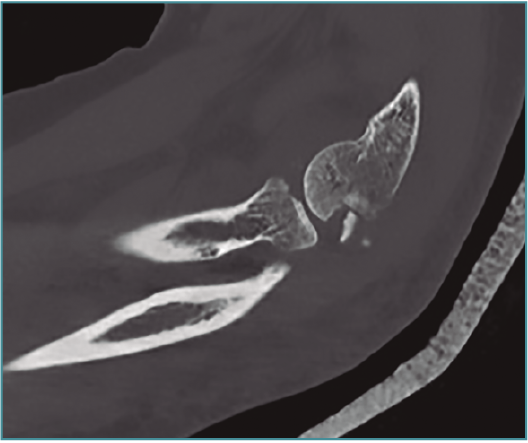

Método: hemos revisado 38 pacientes con codo rígido postraumático o degenerativo que se trataron mediante artrolisis artroscópica entre 2013 y 2016, con un seguimiento medio de 25 meses (38-15). Según la etiología de la rigidez, clasificamos a los pacientes en 2 grupos: grupo 1, los pacientes con rigidez por patología degenerativa del codo, y grupo 2, los pacientes con rigidez postraumática. Clasificamos la rigidez siguiendo la escala de Morrey y utilizamos la escala funcional Mayo Elbow Performance Index (MEPI), que evalúa el dolor, la movilidad, la estabilidad y la función del codo pre- y postoperatoriamente. Describimos los procedimientos artroscópicos realizados en cada paciente, que incluyen la sinovectomía, el desbridamiento de tejido fibroso, la capsulectomía anterior y/o posterior, la resección de osteofitos en la parte anterior y posterior del codo, la extirpación de cuerpos libres y la liberación “abierta” del nervio cubital.

Method: a review was performed on 38 patients with stiff elbow due to degenerative or post-traumatic reasons, and who were treated by arthroscopic arthrolysis between 2013 and 2016, with a mean follow-up of 25 months (38-15). Elbow stiffness was classified following the Morrey scale and the Mayo Elbow Performance Index (MEPI) functional scale was used to evaluate pain, mobility, stability and elbow function pre- and post-operatively. The arthroscopic procedures performed on each patient are described, including synovectomy, debridement of fibrous tissue, anterior and/or posterior capsulotomy, resection of osteophytes in the anterior and posterior part of the elbow, extirpation of loose bodies and open release of the ulnar nerve.